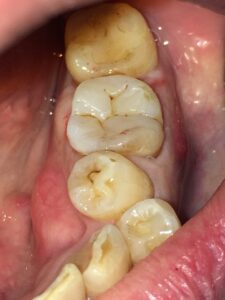

術後写真。臨在歯に色調を合わせ咬合面にもステインを付け自然な感じに修復しました。

(ステインについては真っ白に修復したいという方も多いので、患者さんと相談して付けるかどうか決めています)

治療回数:1回(約60分)

かなりマニアックな治療法ではありますが、当院では条件によりますがこのような治療法を選択することもできます。

※自由診療(¥55,000~66,000税込)となります。

※材料の強度を考えるとゴールドやセラミックのほうが高くなります。

※咬合力が非常に強い場合は適応外になります。